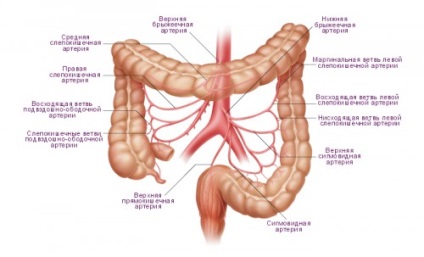

Structura colonului uman

Situat în partea de jos a intestinului, acesta este absorbit de fluid din chim - chim, scaun format.

- intestin orb și apendice - forme apendice vierme

- Colon - aceasta include în creștere, poperechnoobodochnaya, descendent, colon sigmoid

- Direct - fiolă - o parte largă și o îngustare a vârfului, care se încheie anus.

mucoasă colonică, fără scame, cu o mulțime de criptelor. Longitudinale, fibre musculare netede circulare sunt teaca de colon.